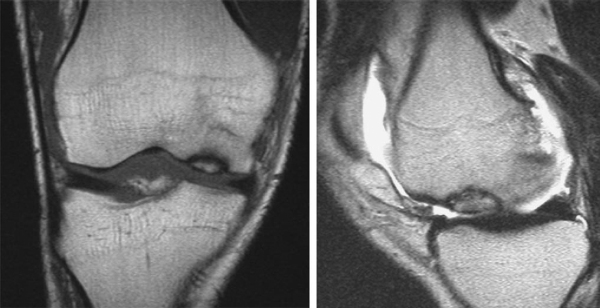

Magnetic resonance imaging is the “gold standard” for osteochondral lesions (

Fig. 56-2

). Fluid or edema behind the lesion is suggestive of an unstable fragment.

Evaluate the extent and depth of osseous involvement. Beware of high sensitivity for subchondral edema, which leads to false positives for osseous disease.